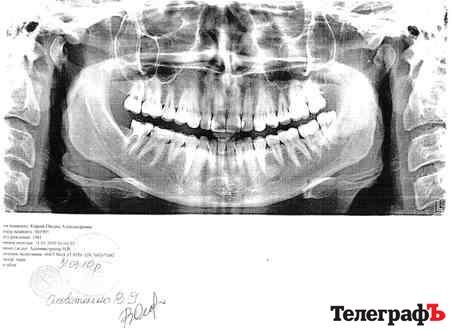

– У мене перелом на щелепі, через який я не можу вже нормально розмовляти, – каже Оксана, – його зафіксували на знімках, які я зробила у приватній клініці на сучасному обладнанні. Але ці знімки в СМЕ назвали «фотошопом» і відмовляються надавати висновки про ступінь тяжкості тілесних ушкоджень. А без них не може бути порушено кримінальну справу, а я не можу домогтися справедливості. Міліція відмовила у порушенні справи через відсутність висновків.

Першого квітня Оксана написала заяву в прокуратуру стосовно дій судмедексперта, але досі ніякого реагування не відчула. Джерело у СМЕ «Телеграфу» повідомило, що потерпілій запропонували пройти додаткове обстеження, тому що жоден лікар у Кременчуці та Полтаві не захотів описувати знімки, які роздруковані з комп‘ютера. Оксана ж відмовляється від нього, оскільки додаткове «опромінення» лише завдасть шкоди її здоров‘ю.